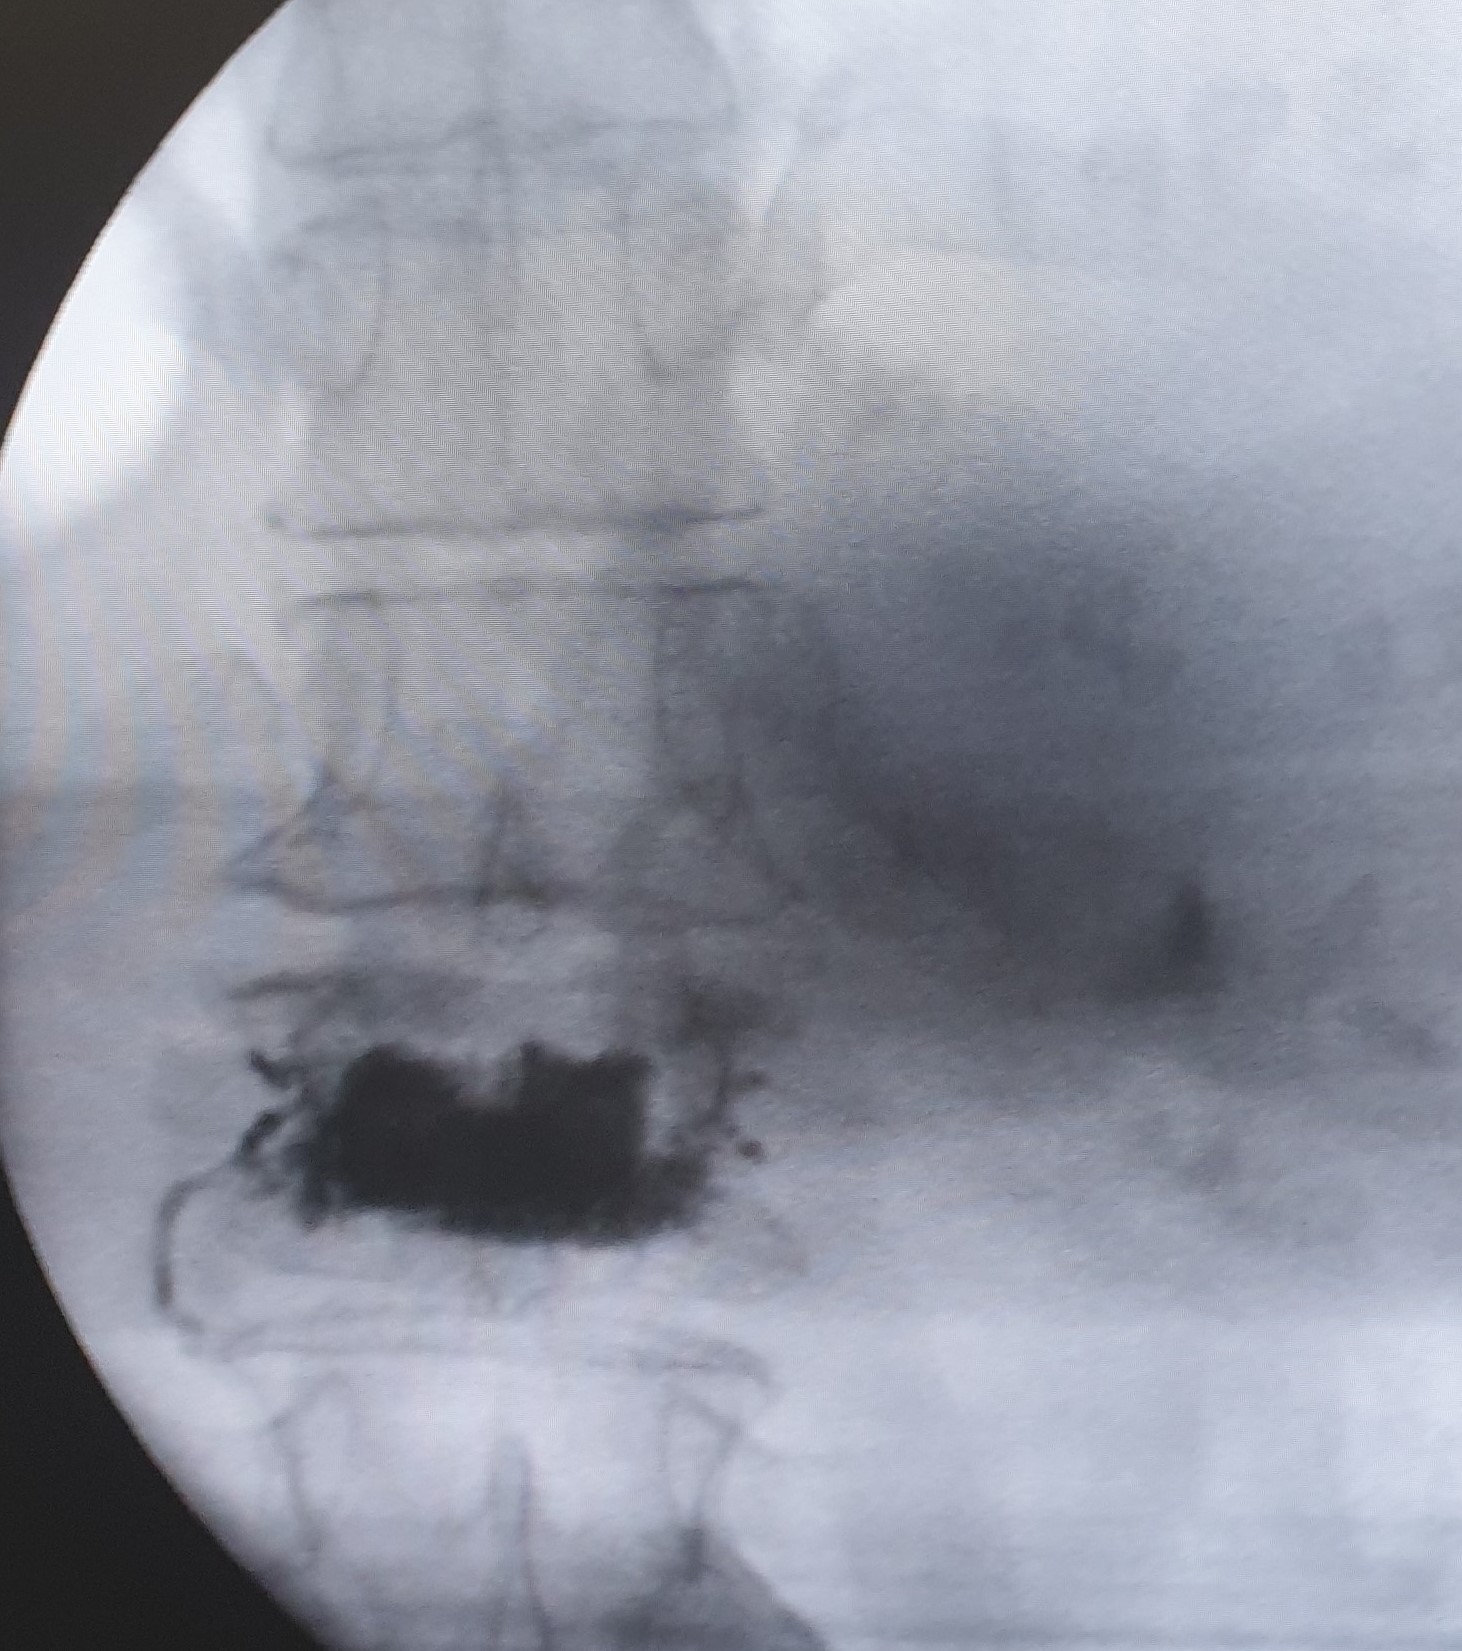

Πρόκειται για συμπιεστικά κατάγματα των σπονδύλων που προκαλούν έντονο πόνο, περιορισμένη κίνηση και ενίοτε κυφωτική παραμόρφωση του σπονδυλικού άξονα. Η κατάρρευση του σπονδυλικού σώματος μπορεί να προκαλέσει πίεση στις νευρικές δομές του σπονδυλικού καναλίου με ανάπτυξη αντίστοιχης νευρολογικής σημειολογίας. Τα οστεοπορωτικά κατάγματα παρατηρούνται συχνότερα στην θωρακική και στην οσφυική μοίρα της σπονδυλικής στήλης και μπορεί να είναι μονήρη ή πολλαπλά.

Ποια είναι η κατάλληλη θεραπευτική προσέγγιση των οστεοπορωτικών καταγμάτων

Η θεραπευτική αντιμετώπιση πρέπει να στοχεύει στη μείωση του πόνου, στην αποκατάσταση της σταθερότητας της σπονδυλικής στήλης και στην αποτροπή της κυφωτικής παραμόρφωσης του σπονδυλικού άξονα.

- Κυφοπλαστική και σπονδυλοπλαστική